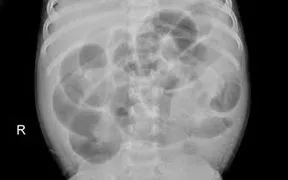

Tại Khoa Ngoại Tổng hợp, sau khi khám lâm sàng và thực hiện các xét nghiệm cần thiết, các bác sĩ xác định trẻ bị tắc ruột - một cấp cứu ngoại khoa có thể dẫn đến hoại tử ruột, nhiễm trùng ổ bụng và đe dọa tính mạng nếu không xử trí kịp thời.

Ngay lập tức, ekip bác sĩ đã tiến hành phẫu thuật cấp cứu kết hợp hồi sức tích cực. Sau quá trình điều trị và theo dõi sát sao, sức khỏe bệnh nhi tiến triển tốt. Sau mổ khoảng 10 giờ, trẻ đã đại tiện trở lại, bụng mềm, ăn bú tốt và đang tiếp tục được chăm sóc tại khoa, dự kiến xuất viện trong tuần.